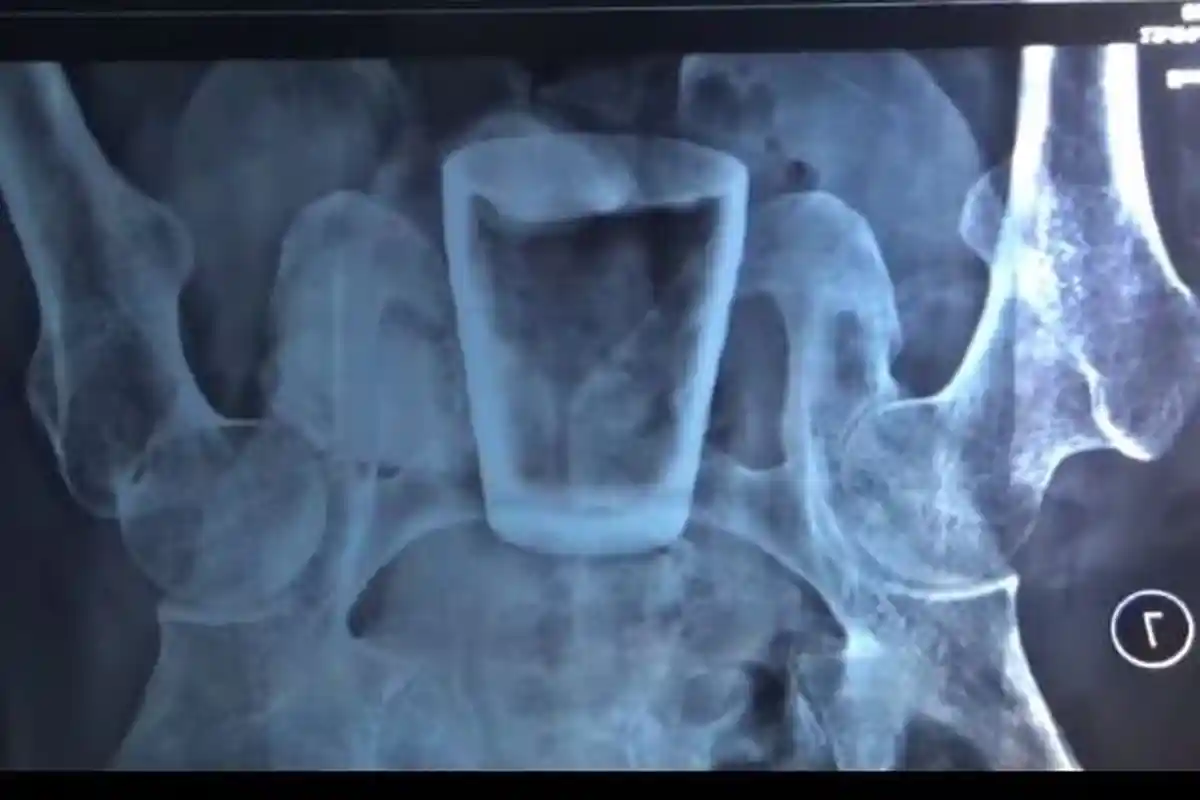

Pasien yang mengeluh nyeri di perut itu diperiksa dan menjalani rontgen.

“Kami foto rontgen dulu, ternyata ditemukan bentukan berupa gelas,” kata Doddy.

Berdasarkan foto rontgen itu, terlihat gelas kaca di dalam tubuh Lasiadi.